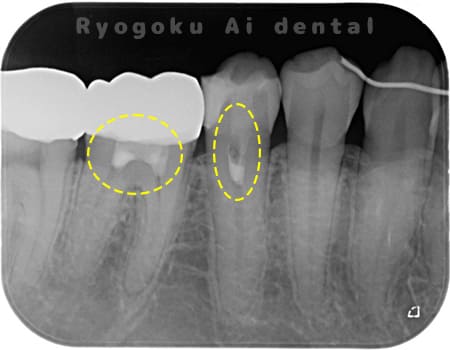

Case04

-

- 原因

- C3、重度カリエス

- 治療内容

- 17・15断髄治療

- 治療費用

- 154,000円

他院で神経をとるほどの虫歯があり、神経を残したいとのことで来院された患者様です。歯の神経を一部分取る断髄治療を行い、問題なく経過を追っています。

<リスク・副作用>

術後は痛み、腫れ、痺れなどの副作用が生じる場合があります。症状が再発する可能性があります。その場合は抜髄する必要があります。